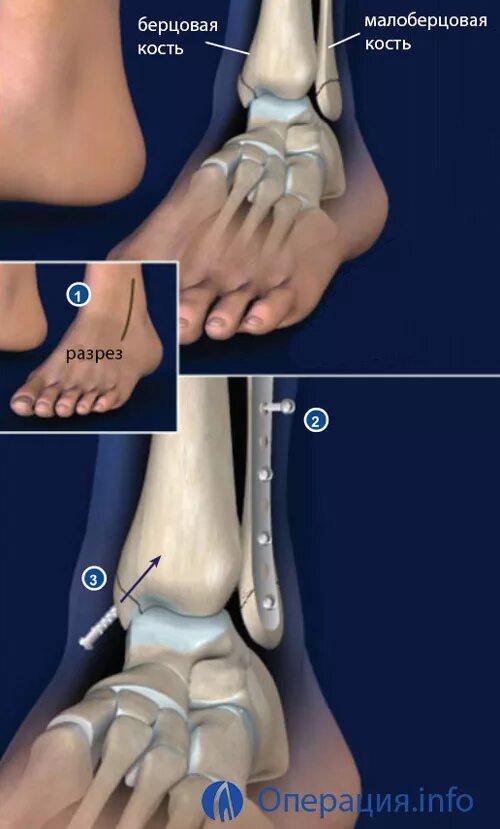

Лодыжка перелом смещение операция пластина